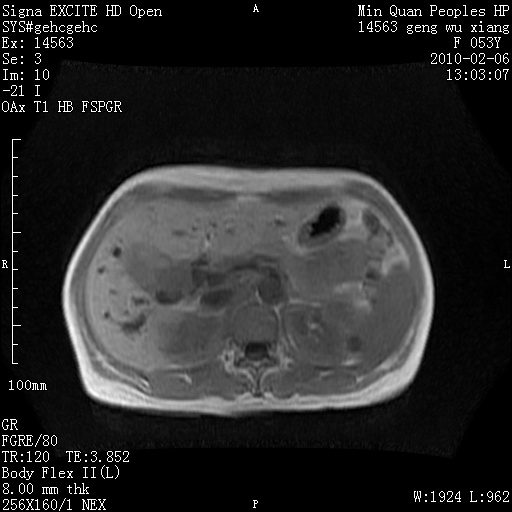

标题: MRI2762:胆道梗阻原因?

f,53y,全身黄染多日。

高位胆道梗阻 胆管癌可能性大

支持 高位胆道梗阻 胆管癌可能性大。